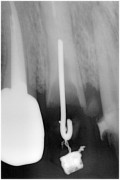

写真はむし歯で歯冠部がなくなってしまった歯、通常抜歯になりますが、

歯根の長さがある場合、矯正力により牽引し保存します。